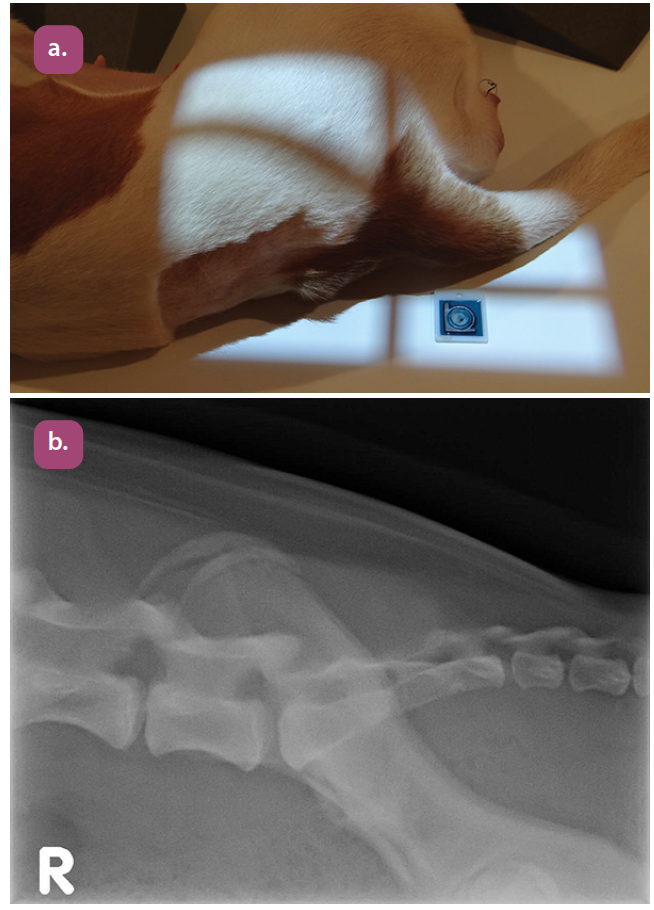

lateral thoracic spine projection

lateral thoracolumbar spine projection

lateral lumbar spine projection

lateral lumbosacral projection